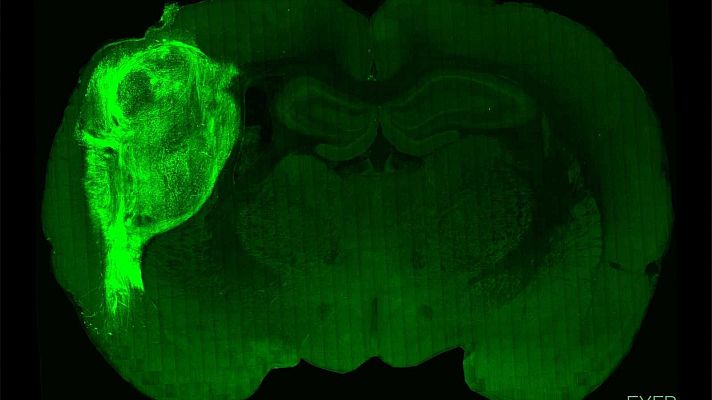

Implantan 'minicerebros' humanos en ratas recién nacidas y logran influir en su comportamiento

Un equipo de científicos de la Universidad de Stanford en EEUU ha conseguido trasplantar neuronas humanas al cerebro de ratas recién nacidas y...